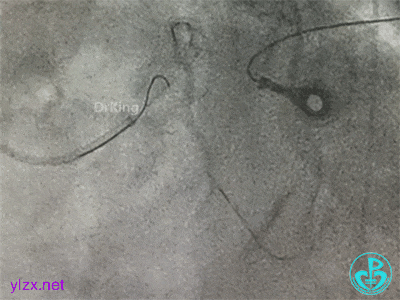

导丝Rewire回旋支,非顺应性球囊分别后扩张前降支和回旋支支架,对吻扩张。

患者术中血压偏低,一度出现烦躁。及时IABP置入是手术能顺利完成的保障。术前的准备很全面,造影结果如下。